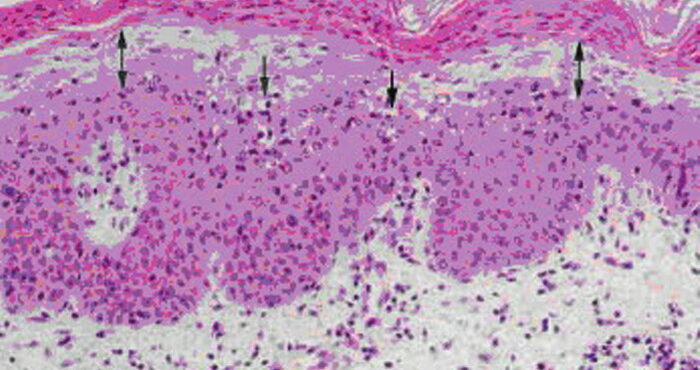

Necrobiois lipoidica diabeticorum = النخر الشحماني السكري Necrobiosis Lipoidica Necrobiosis lipoidica is an idiopathic disorder typified by indurated plaques of the shins . In 1966, in a large series, Muller and Winkelman reported that two thirds of patients with necrobiosis lipoidica had overt diabetes at the time of diagnosis {82}. Of the rest, all but […]